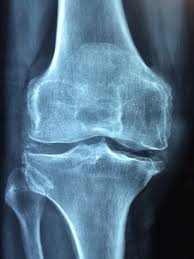

콘드로이친은 관절 내 연골을 보호하고 윤활 작용을 강화합니다. 퇴행성 관절염 증상 완화에 도움을 줄 수 있습니다. 관절의 뻣뻣함과 통증을 줄여 움직임을 개선합니다. 장기간 복용 시 관절 기능 유지에 유리합니다. 관절 질환 환자들에게 널리 권장되는 보충제입니다.

2) 연골 보호

연골을 구성하는 주요 성분 중 하나로, 손상된 연골의 재생을 돕습니다. 연골 퇴행을 늦추는 역할을 합니다. 특히 노인에게 효과적입니다. 글루코사민과 병용 시 효과가 더욱 커집니다. 관절 구조의 안정성을 높여줍니다.

5) 뼈 건강 강화

연골 보호와 함께 뼈 밀도 유지에도 기여할 수 있습니다. 골다공증 예방에 긍정적인 영향을 줄 수 있습니다. 칼슘·비타민D와 함께 섭취하면 시너지 효과가 있습니다. 노년기 뼈 건강 관리에 도움이 됩니다. 전반적인 근골격계 건강에 기여합니다.